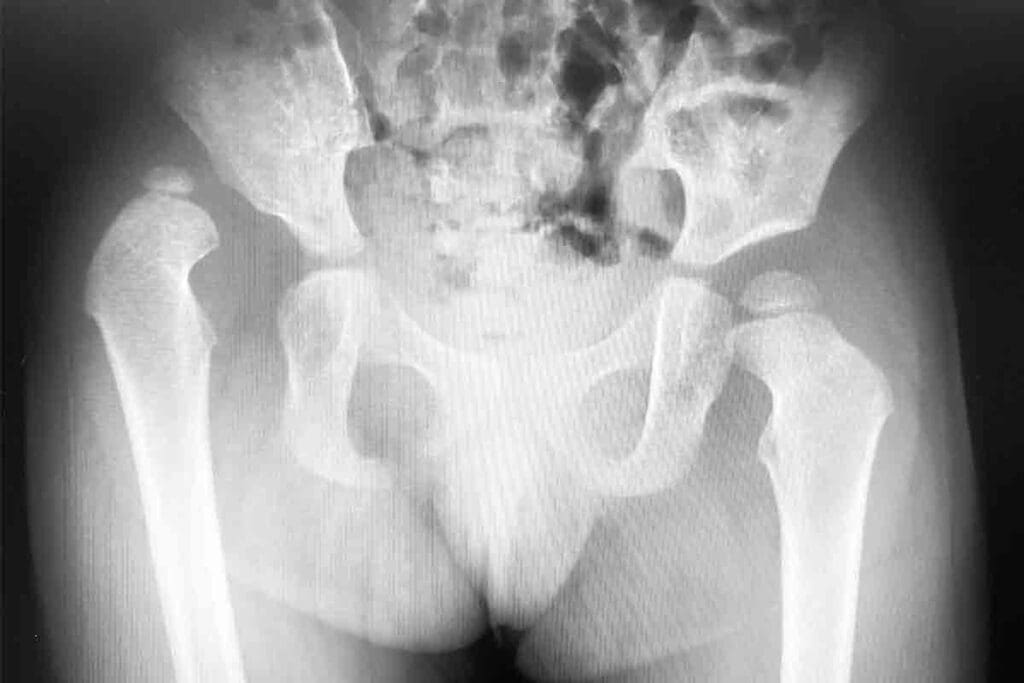

Anatomical Considerations of Hip Sarcomas

The hip area is complex, with the femur, pelvis, and soft tissues like muscles and fat. Sarcomas can start in any of these, making diagnosis and treatment hard.

Understanding the anatomy is important for knowing the sarcoma type and its effects. Bone sarcomas can weaken bones, leading to fractures. Soft tissue sarcomas can cause pain and affect movement because of their location near joints and nerves.

Imaging Modalities and Their Importance

Imaging studies are key in diagnosing hip sarcoma. We first use X-rays to check bone health and look for any issues. For a closer look, we often use Magnetic Resonance Imaging (MRI) and Computed Tomography (CT) scans.

MRI is great for soft tissue sarcomas, giving us detailed images of the tumor and its surroundings.

Positron Emission Tomography (PET) scans help us see how active the tumor is and if it has spread. These imaging tools help us accurately diagnose and stage hip sarcoma, guiding our treatment plans.